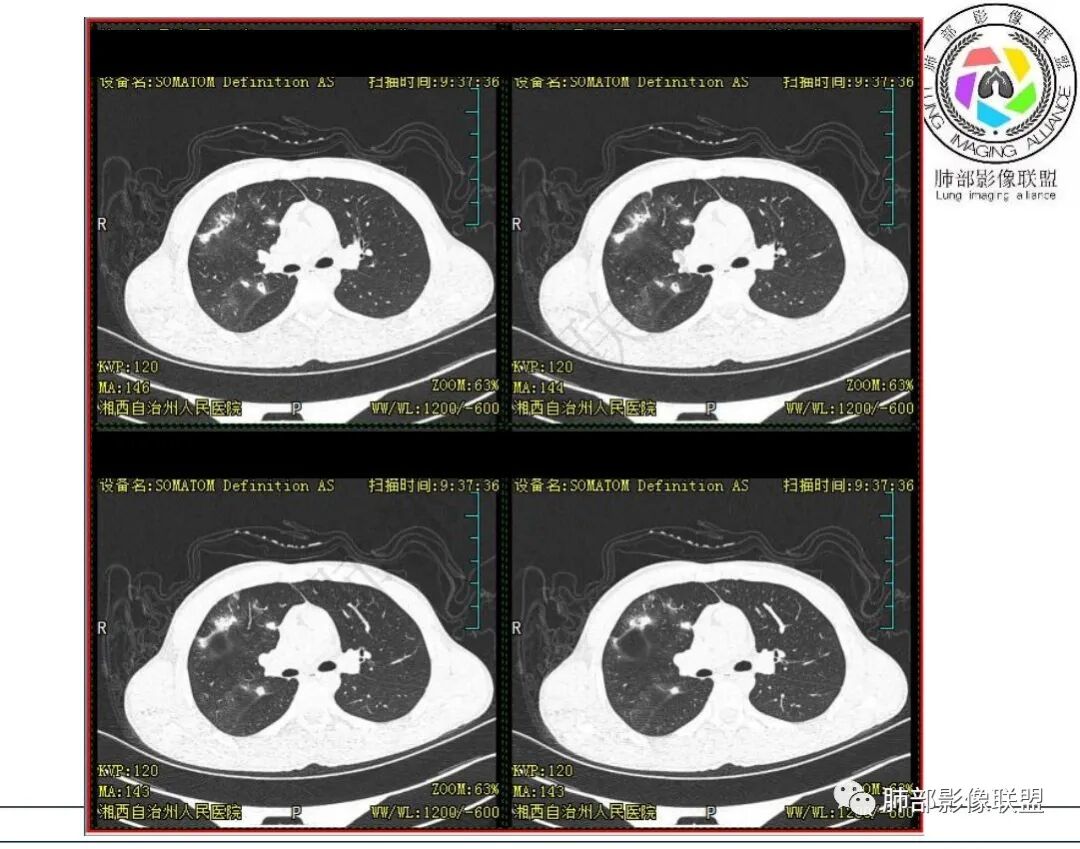

影像:右肺上叶多发实变影结节影,边界模糊,边缘收缩,伴多发空洞,洞壁光滑,部分支气管壁增厚。

3.首次CT提示:右肺上叶多发结节影及实变影,簇状分布,周围散在磨玻璃影,结节内多类圆形空洞,内壁光整,有一定张力,偶见液平。部分支气管壁增厚。

考虑良性感染性病变可能。